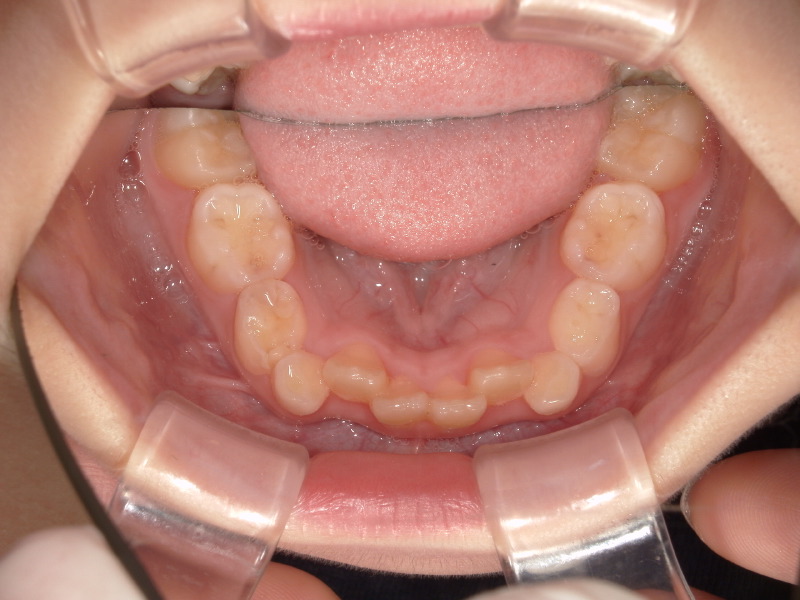

3ヶ月の経過

マウスピースとアクティビティーを3ヶ月続けた経過です。

入れなかった歯が少しずつ綺麗に並んでいいアーチになってきています。

マウスピースをいれて寝ると朝少し動いてるような痛みがあったそうです。

痛みがあるといってくれる子も少し、といった程度です。